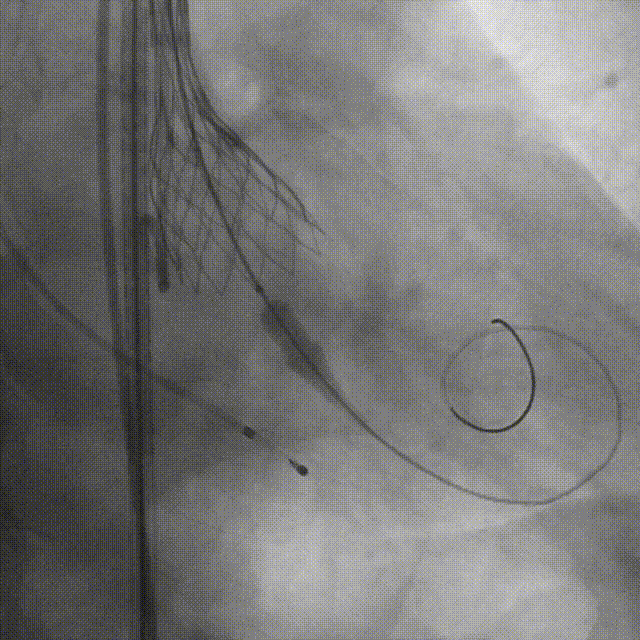

最终形态造影

检查入路完好